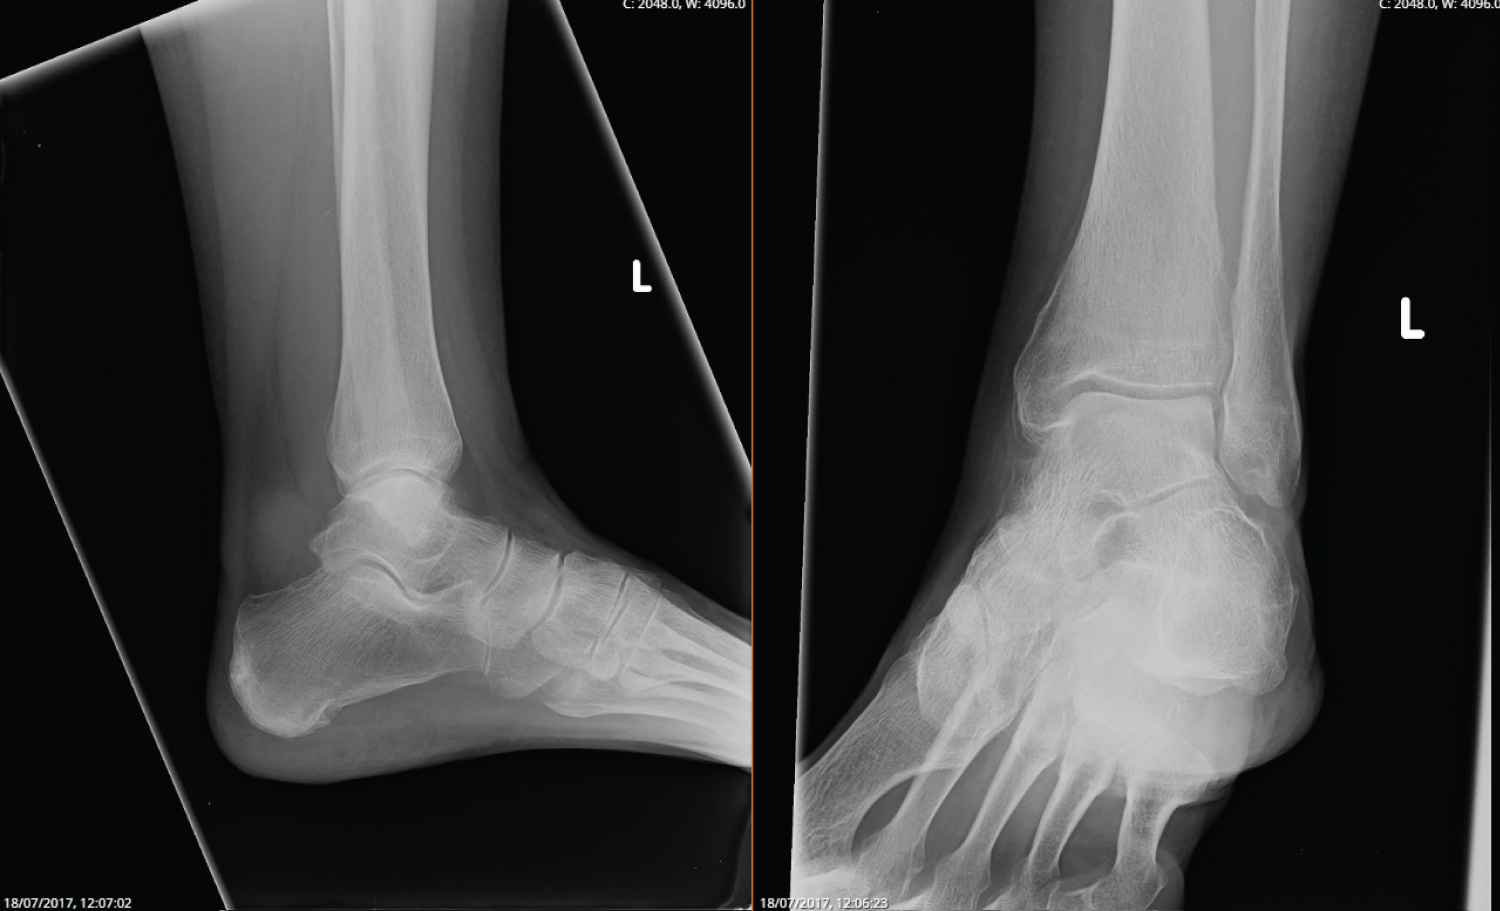

An 81-year-old female had ongoing pain in her left ankle for the past 7 years. It was initially thought to be an ankle sprain when she first presented and was managed non-operatively with analgesia and physiotherapy. She denies any trauma and has been able to weight bear and mobilise on her left leg. There was swelling in the medial aspect of the ankle and with repeated episodes of pain, a plain X-ray was performed. An ankle cyst was found and the patient underwent excision of this cyst. The excisional biopsy provided a diagnosis of synovial chondromatosis. The patient re-presented three years later with massive swelling, severe pain day and night, minimal mobility desperate for a solution. X-ray and MRI findings are seen below (Figure 1 and Figure 2).

Figure 1: X-ray of the left ankle joint performed in 2017 showing edema and calcification of soft tissue. View Figure 1

On examination, the patient's left ankle had reduced range of motion in flexion and extension as compared to the right. There was swelling of the left ankle with tenderness in the medial region with sural nerve paraesthesia on the lateral side of the foot. No other bony tenderness was present.